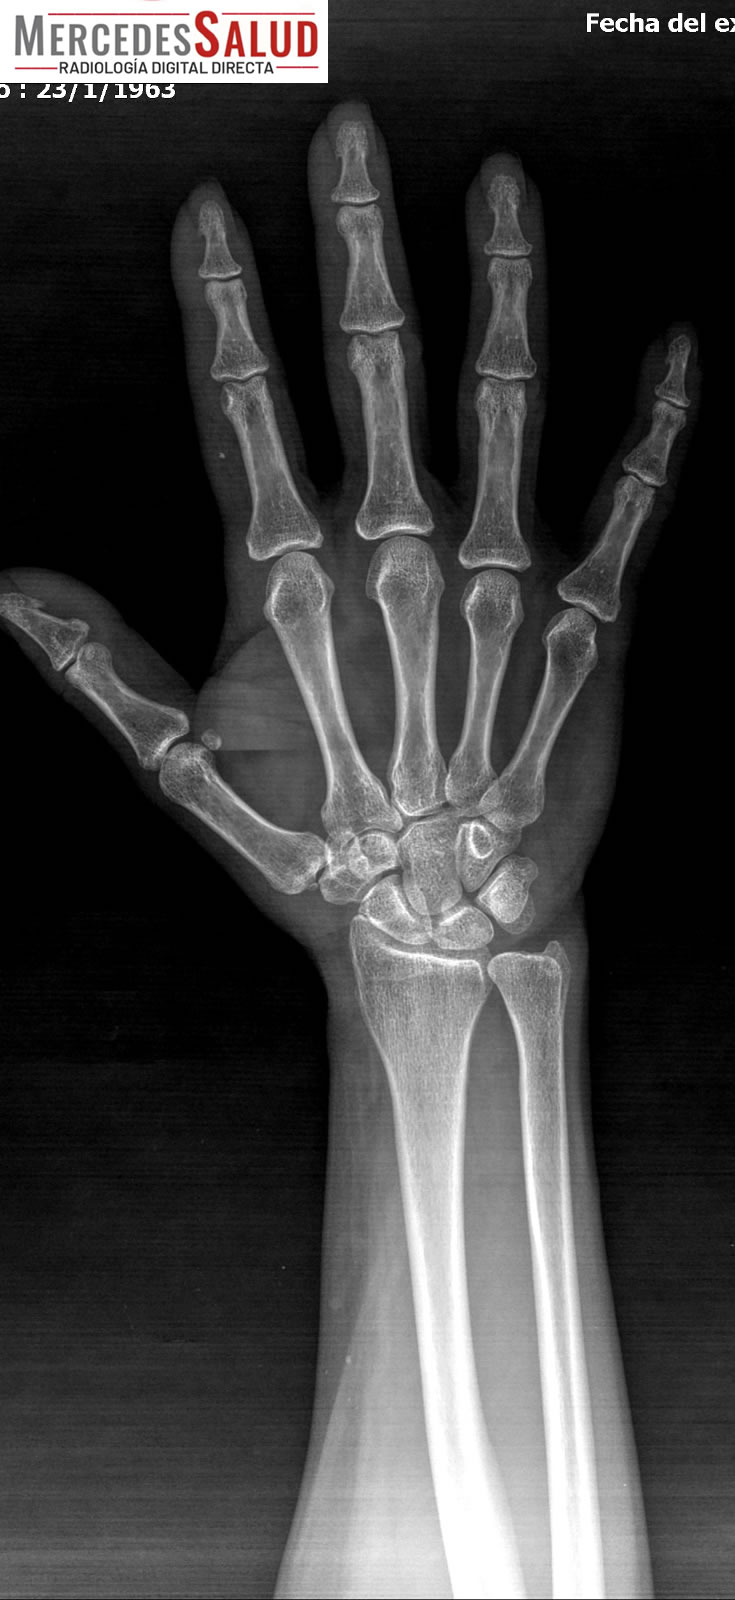

Amplio espectro de estudios

Además del tomógrafo dental, que realiza panorámicas dentales y tomografías, y permite realizar laminografías de la articulación temporomandibular (ATM) y placas de macizo facial para casos como fracturas, el servicio también ofrece estudios especializados como espinogramas y mediciones de miembro inferior con el equipo Pimax. Estos estudios de alta calidad son muy requeridos por traumatólogos de la ciudad y zonas aledañas. La calidad de imagen es tal que, según el Lic. Quiroga, pacientes de ciudades vecinas viajan a Mercedes para ser atendidos.

Un punto fundamental a destacar es la baja dosis de irradiación que reciben los pacientes. Al tratarse de equipos modernos, la exposición es mínima, un factor que es complementado con estrictas medidas de seguridad, incluyendo el uso de protección personal plomada (chaleco y tiroides) para quienes asisten.